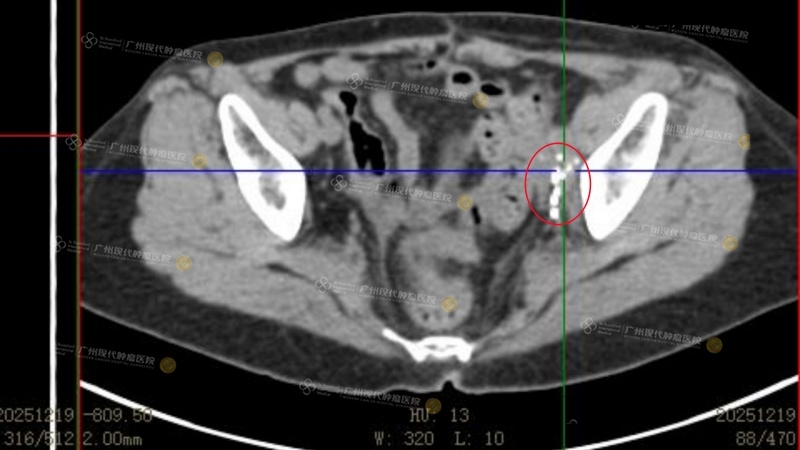

ผลการรักษาปรากฏชัดอย่างรวดเร็ว—หลังการรักษาครั้งแรกเสร็จสิ้นอาการปวดท้องที่ทรมานเธอมานานก็หายไปหลังการรักษาครั้งที่สองการไหลเวียนเลือดที่ขากลับมาดีขึ้นอาการบวมของขาซ้ายลดลงอย่างเห็นได้ชัด“สิ่งนี้ทำให้ฉันมีความมั่นใจอย่างมาก” ฟู อ้ายฉินเล่าด้วยความตื่นเต้น“หลังจบการรักษาครั้งที่สี่ ได้ทำการตรวจ PET Scanก็เห็นได้ชัดจริงๆว่าก้อนมะเร็งหดเล็กลงอย่างมาก”ตลอดระยะเวลาการรักษา 3 เดือน จนถึงปัจจุบันต่อมน้ำเหลืองในอุ้งเชิงกรานของฟู อ้ายฉินแทบจะไม่มีกิจกรรมของโรคเหลืออยู่แล้ว ก้อนมะเร็งที่ตับ หายไปโดยไม่พบรอยโรคการประเมินผลการรักษาโดยรวมสามารถจัดอยู่ในระดับ PR

(หลังรักษา 4 ครั้ง ผลตรวจติดตามเมื่อวันที่ 19 ธันวาคม 2025 แสดงให้เห็นว่าก้อนมะเร็งแทบจะไม่มีกิจกรรมหลงเหลืออยู่แล้ว)